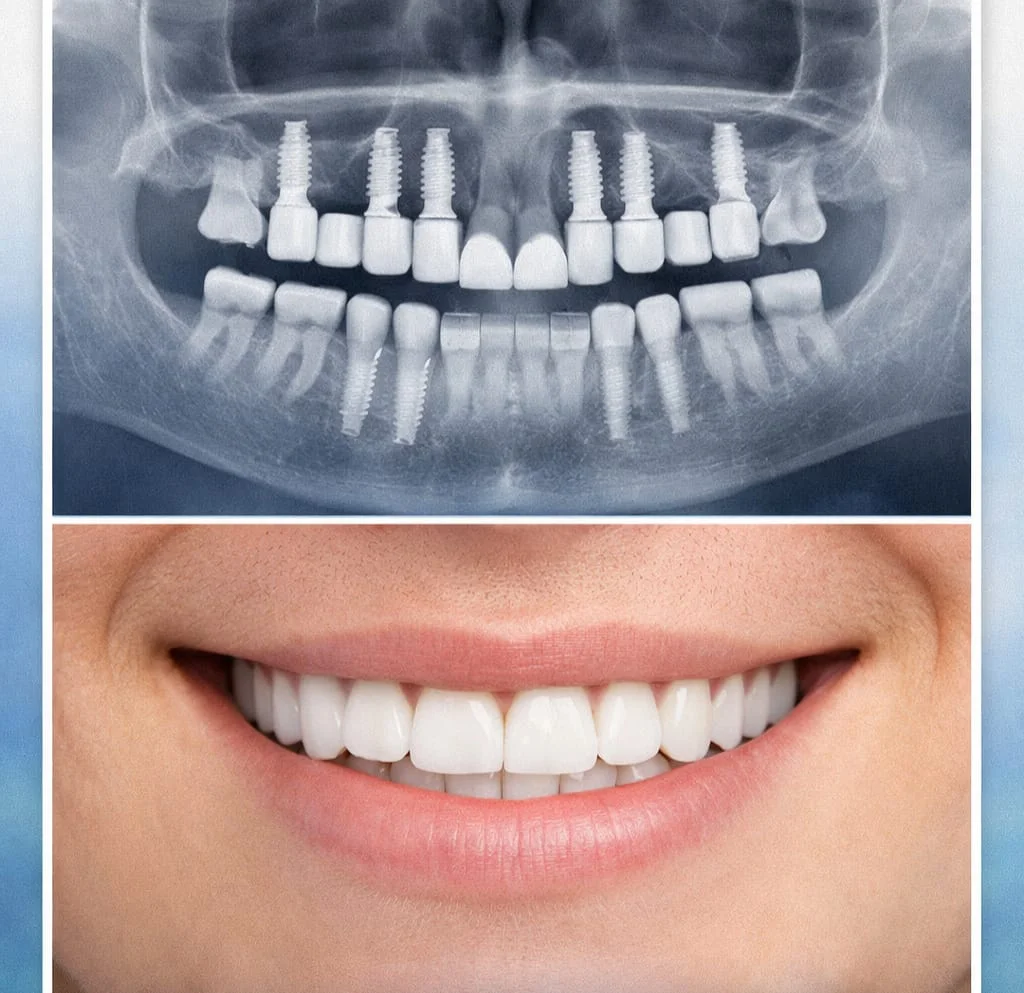

O implante é um componente instalado no osso para substituir a raiz do dente perdido. Depois da integração com o osso, ele passa a receber a reabilitação protética que devolve forma e função.

Já o enxerto ósseo entra quando o osso da região não oferece volume ou qualidade suficientes para sustentar o implante com segurança. Nem todo paciente precisa de enxerto, mas quando ele é indicado, faz parte do planejamento para melhorar previsibilidade.